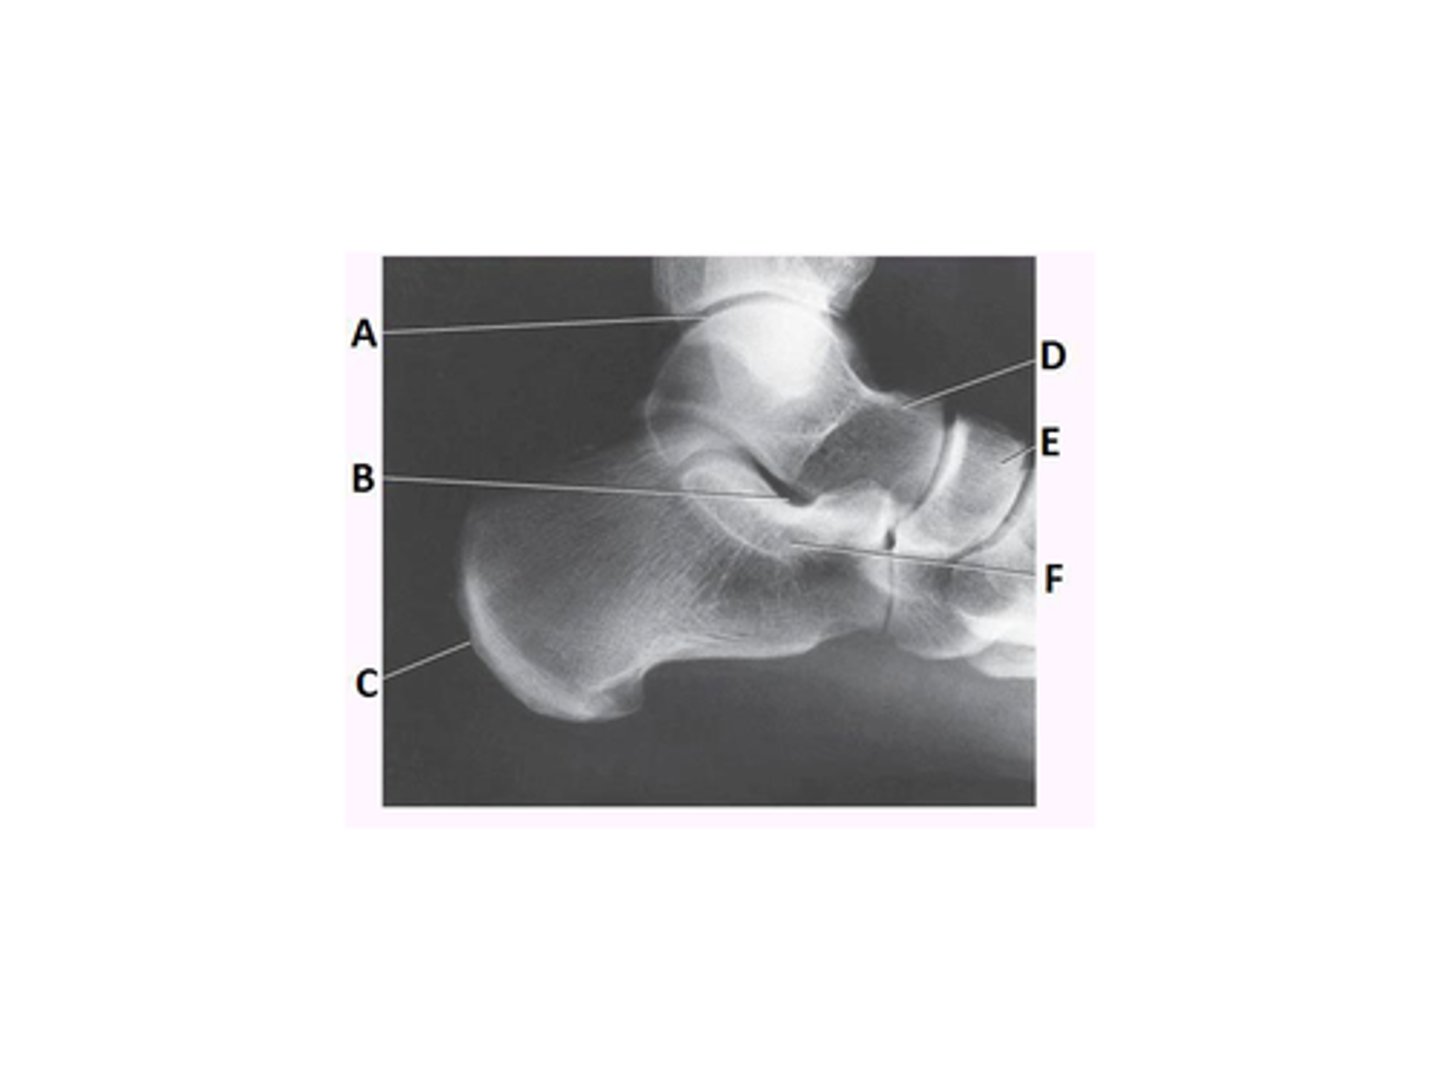

What anatomy is labeled as letter E in the image below?

Mortise joint

Tibiotalar joint

Navicular

What anatomy is labeled as letter D in the image below?

Talus

Sinus tarsi